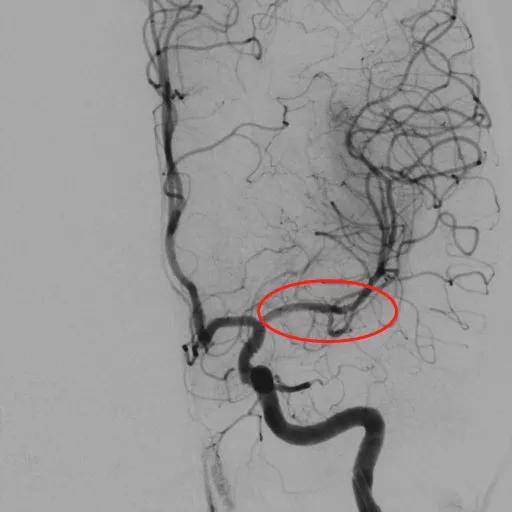

经股动脉或者桡动脉穿刺,置入动脉鞘管;经动脉鞘管将指引导管置入病变血管;将微导丝通过颅内动脉狭窄部位远端血管,使用球囊导管进行预扩张;根据血管大小选择相应的支架推送到狭窄部位并释放。

支架成形术后,左侧大脑中动脉血流复通